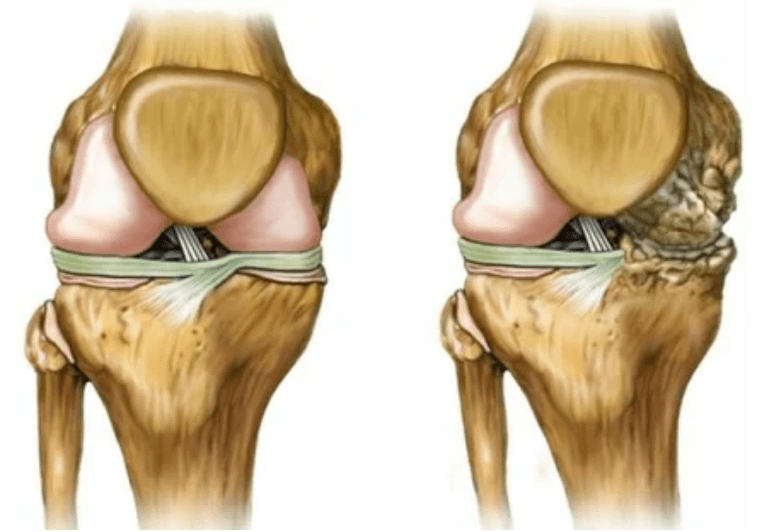

L'arthrose de l'articulation se développe pendant longtemps, n'affecte initialement que le cartilage Hyalin, puis se propage aux os, implique la coquille synoviale, les muscles et toute la capsule articulaire. Au premier ou au début de l'arthrose, la lésion se manifeste légèrement: de petites douleurs après un travail acharné, un gonflement, une rougeur de la peau. En raison de l'ignorance des sensations inconfortables, l'articulation est déformée, enflammée, apporte une douleur intense, leur pic de chute le matin. La maladie se caractérise par la disparition de la douleur après le développement de l'articulation. S'il n'est pas traité, une personne perd complètement la mobilité de l'articulation.

- Déformation articulaire, le cartilage acquiert une forme irrégulière, provoquant une courbure;

- 3 degrés. Souvent, il y a des douleurs, il est difficile de déplacer le membre en raison de changements dans l'articulation. Les lésions sont étendues, deviennent perceptibles au look nu. La déformation du site conjoint se produit, la zone affectée gonfle et devient rouge. L'axe des membres est perturbé, ce qui conduit à la complexité du mouvement. Les changements pathologiques provoquent le raccourcissement des ligaments. Les sous-lieux et les contractures apparaissent. Les muscles adjacents sont raccourcis ou étirés, à partir de laquelle la fonction contractile est affaiblie.